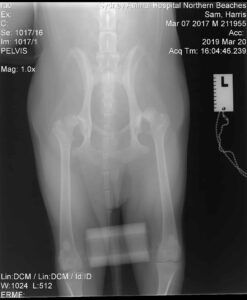

Our canine hero came to us with a history of pain in his left hind leg, which had been present since he was a puppy. In his first consultation, with Northern Beaches Practice owner Dr. Ben Brown , we were told by his owners that Sam had never been able to run or jump properly and was usually slow to rise. Border Collies as a breed are commonly known for their athletic ability, high intellect & high energy, so hearing that Sam did not fit the normal profile immediately raised a red flag. Dr. Ben performed a full health assessment, including manipulating specific joints and limbs, and reviewed radiographs of Sam’s hips that had previously been taken. The diagnosis became clear, Sam was suffering from a condition called Hip Dysplasia.

Once on the operating table the specialist surgeon Dr. Andrew Levien confirmed yet again that Sam had significant osteoarthritis and his left hip was completed luxated. With our team of vets and nurses closely monitoring Sam’s vitals throughout the procedure, Dr. Andrew removed the femoral head and neck. A prosthetic hip joint and femoral head were then surgically attached, replacing the hip joint entirely. The final step to the procedure involved taking a set of radiographs to ensure the implant was in the proper position.